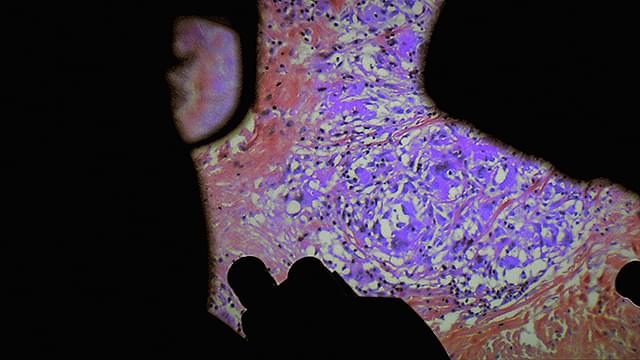

医師の視点から外科手術を見つめ、人体の神秘と人間の恐怖の根源に迫ったドキュメンタリー。

パリ北部近郊の5つの病院のオペ室を舞台に、普段は決して見ることのできない手術時の医師視点のカメラや内視鏡カメラなどの映像を使用しながら、脳や大腸、眼球、男性器などさまざまな外科手術や帝王切開の模様を映しだす。さらに、死と隣りあわせの職場で働く医療従事者たちの心境や、死体安置所での「おくりびと」たちの仕事ぶりをとらえ、医療とは何か、そして肉体と魂とは何かという疑問を探る。